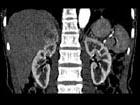

问题 女,35岁,上腹部隐痛不适伴消瘦1月,胃镜提示胃癌,CT扫描如图所示:右侧肾上腺区可见一占位性病灶,应诊断为 ( )

选项 A、右肾上腺嗜铬细胞瘤 B、右肾上腺错构瘤 C、右肾上腺腺癌 D、右肾上腺转移瘤 E、右肾上腺腺瘤

答案 D